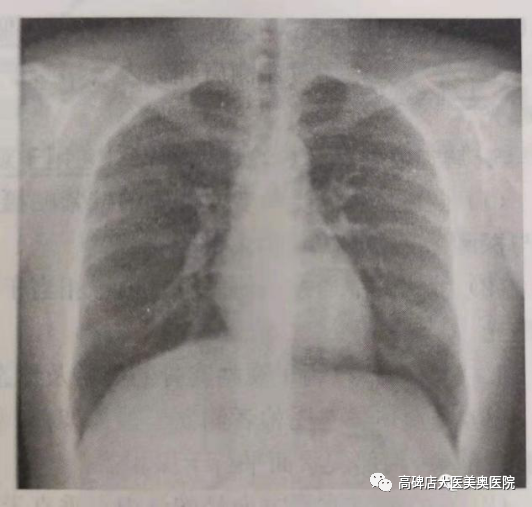

胸部正位摄影体位:受检者面向摄片架站立,双足分开,胸前部紧靠摄片架,双手内旋,手背放于两侧髂骨上,双肩、双臂、双肘贴紧摄片架,两肩放平,下颌置于摄片架上缘,胸部正中矢状面垂直于摄片架中线并重合。

胸部侧位摄影体位受检者挺胸收腹侧立于摄片架前,受检侧紧靠摄影架,双手弯曲高举抱头,使身体的冠状面与探测器垂直,胸壁前后缘与摄片架边缘等距。

胸部正位